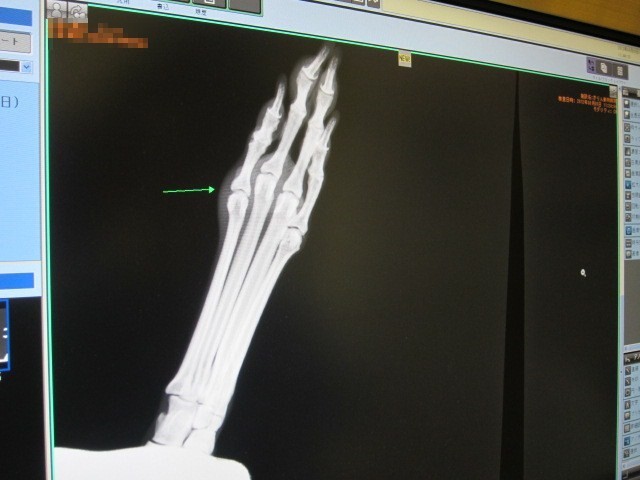

- レントゲン撮影で見たところ、骨はきれい

- どこかでぶつけて中に血が溜まっているか炎症している可能性が高い

ということでまずは抗生物質を一週間服用することになった。